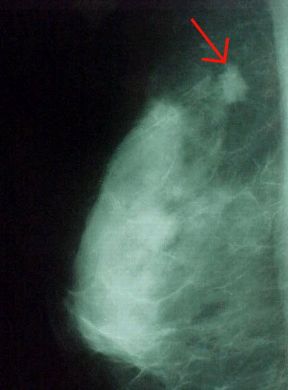

Rappresentazione di una mammografia. Diagnostica. L'esame radiologico diretto della mammella, o mammografia, è un importante strumento di radiodiagnostica. Consente infatti di visualizzare tutte le componenti anatomiche di questa struttura ghiandolare e di evidenziarne eventualmente le alterazioni patologiche. La freccia indica un nodulo mammario neoplastico.